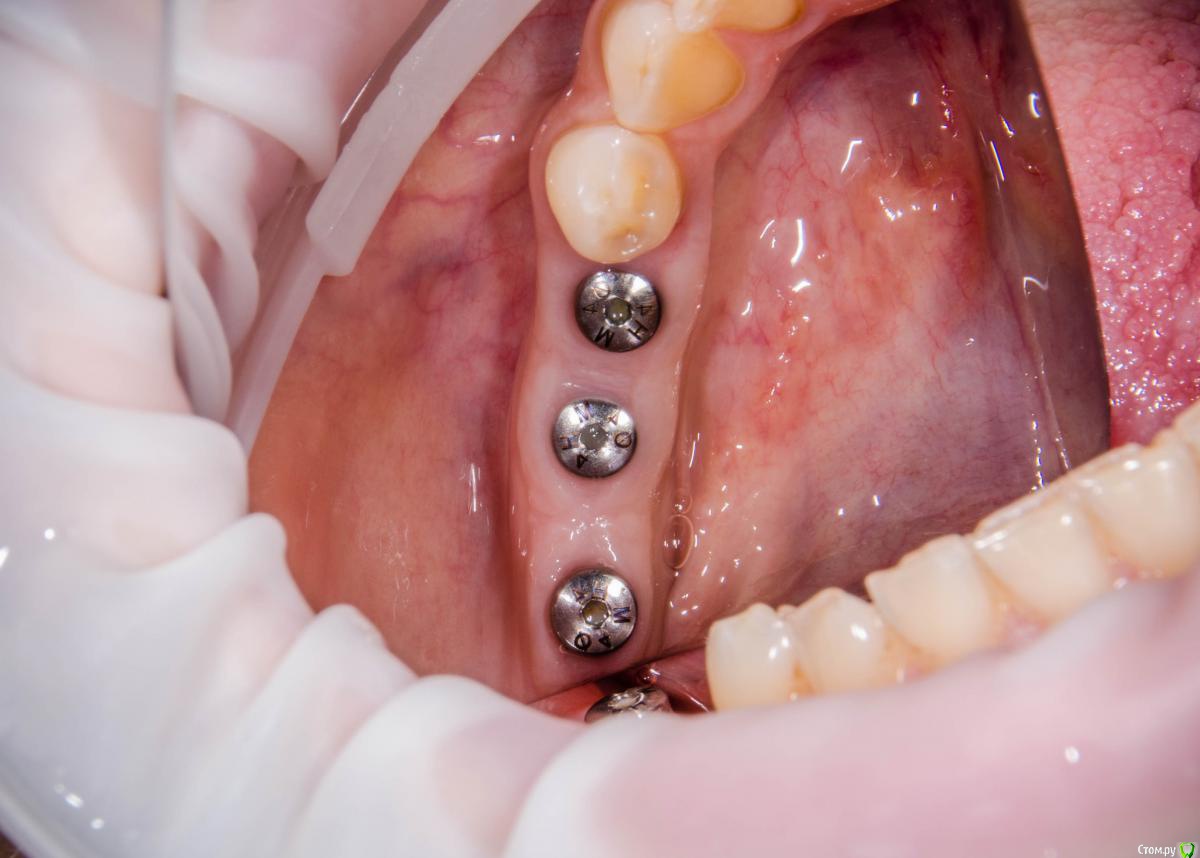

kamranchick Опубликовано 8 февраля, 2017 Автор Поделиться Опубликовано 8 февраля, 2017 Спасибо за публикацию.Какова ширина гребня?5мм сверху в области кристального модуля имплантата дальше около 7мм) Ссылка на комментарий

surf Опубликовано 8 февраля, 2017 Поделиться Опубликовано 8 февраля, 2017 Все же, думаю,карлосс бы здесь расщеплял и добавлял)Десна хорошо получилась Ссылка на комментарий